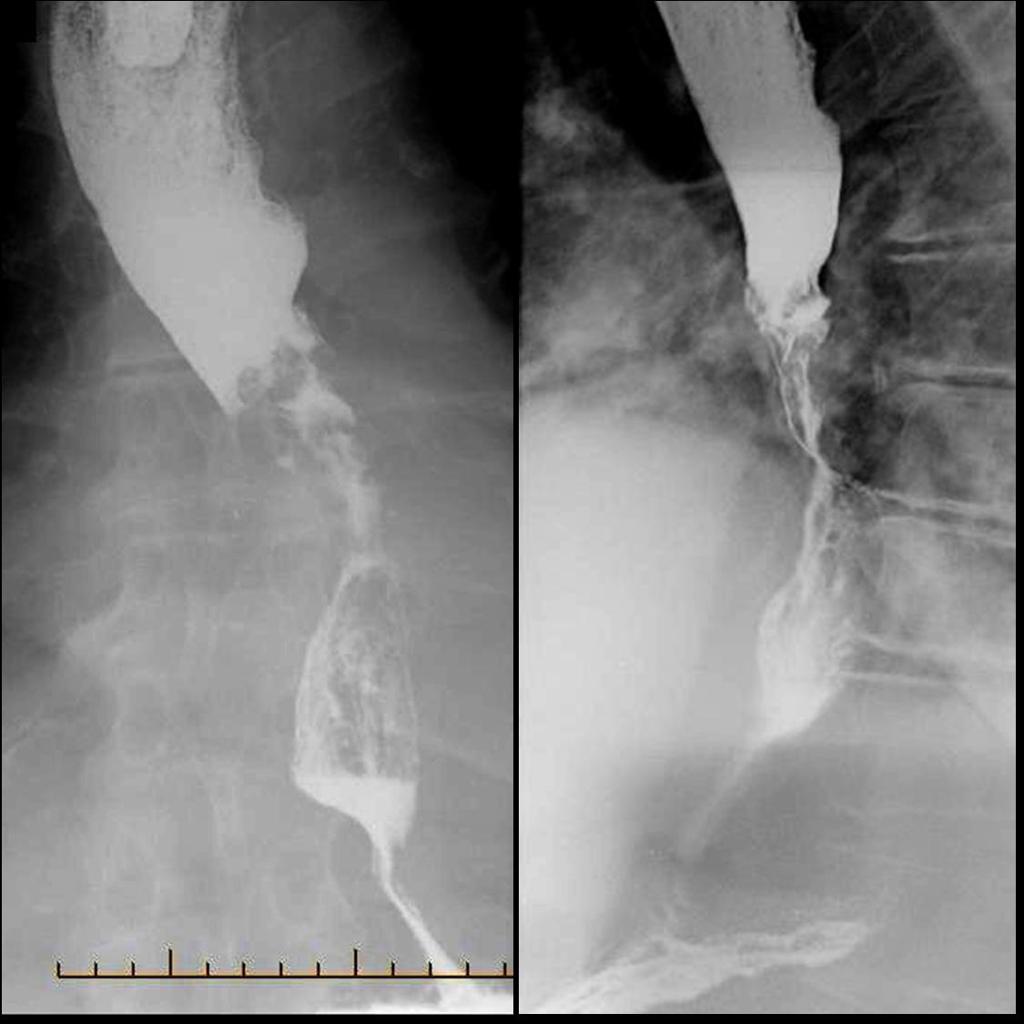

• Рентгенография с бариевым контрастом. Пациент принимает внутрь сульфат бария, который обволакивает стенки пищевода. Это позволяет увидеть на снимке рельеф стенок и обнаружить сужение просвета. На ранней стадии рак может иметь вид небольших круглых выпуклостей, то есть бляшек. На поздней стадии развития новообразование принимает вид большой опухоли неправильной формы, которая может вызывать сильное сужение пищевода. Рентгенография также позволяет диагностировать трахеопищеводную фистулу, то есть когда из-за разрушения новообразованием стенки пищевода на всю толщину пищевод начинает сообщаться с трахеей.

image007-1.jpg Рентгенодиагностика рака пищевода